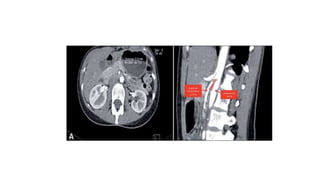

• Diagnosis may follow X-ray examination revealing duodenal

dilation followed by abrupt constriction proximal to the

overlying SMA.

• Standard diagnostic exams include abdominal and

pelvic computed tomography (CT) scan with oral and IV

contrast, upper gastrointestinal series (UGI), and, for equivocal

cases, hypotonic duodenography.

• Criteria in CT scan : is aortomesenteric angle of less than 22

degree and distance of less 10-8 mm. In children, an angle of

less 20 degree.

Diagnosis • Is verydifficult, and usually one of exclusion. • Diagnosis may follow X-ray examination revealing duodenal dilation followed by abrupt constriction proximal to the overlying SMA. • Standard diagnostic exams include abdominal and pelvic computed tomography (CT) scan with oral and IV contrast, upper gastrointestinal series (UGI), and, for equivocal cases, hypotonic duodenography. • Criteria in CT scan : is aortomesenteric angle of less than 22 degree and distance of less 10-8 mm. In children, an angle of less 20 degree. • The reason for the persistence of gastrointestinal symptoms